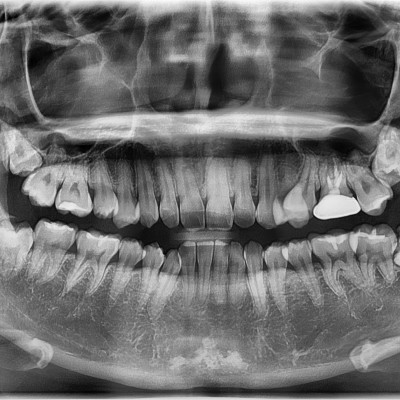

#18,28,38,48 사랑니 발치 #18,28,38,48 사랑니 발치 구강 외과 전문의가 당일 발치했습니다.